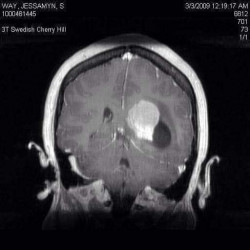

Jessamyn Way

I wore size 23 and had multiple brain tumors. Ive had 6 brain surgeries and failed 18 medications for epilepsy. I now race Triathlons.